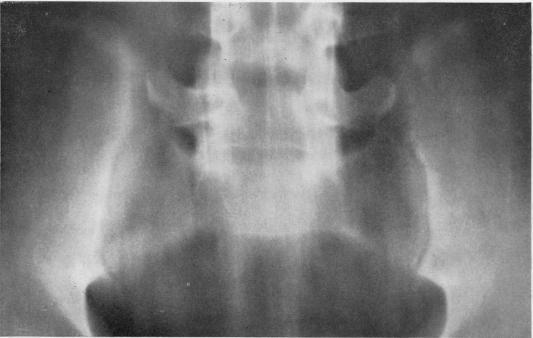

Radiological changes in the sacro-iliac joints and spine of patients with psoriatic arthritis and psoriasis.

Ann Rheum Dis. 1968 Jan;27(1):1-6. doi: 10.1136/ard.27.1.1.